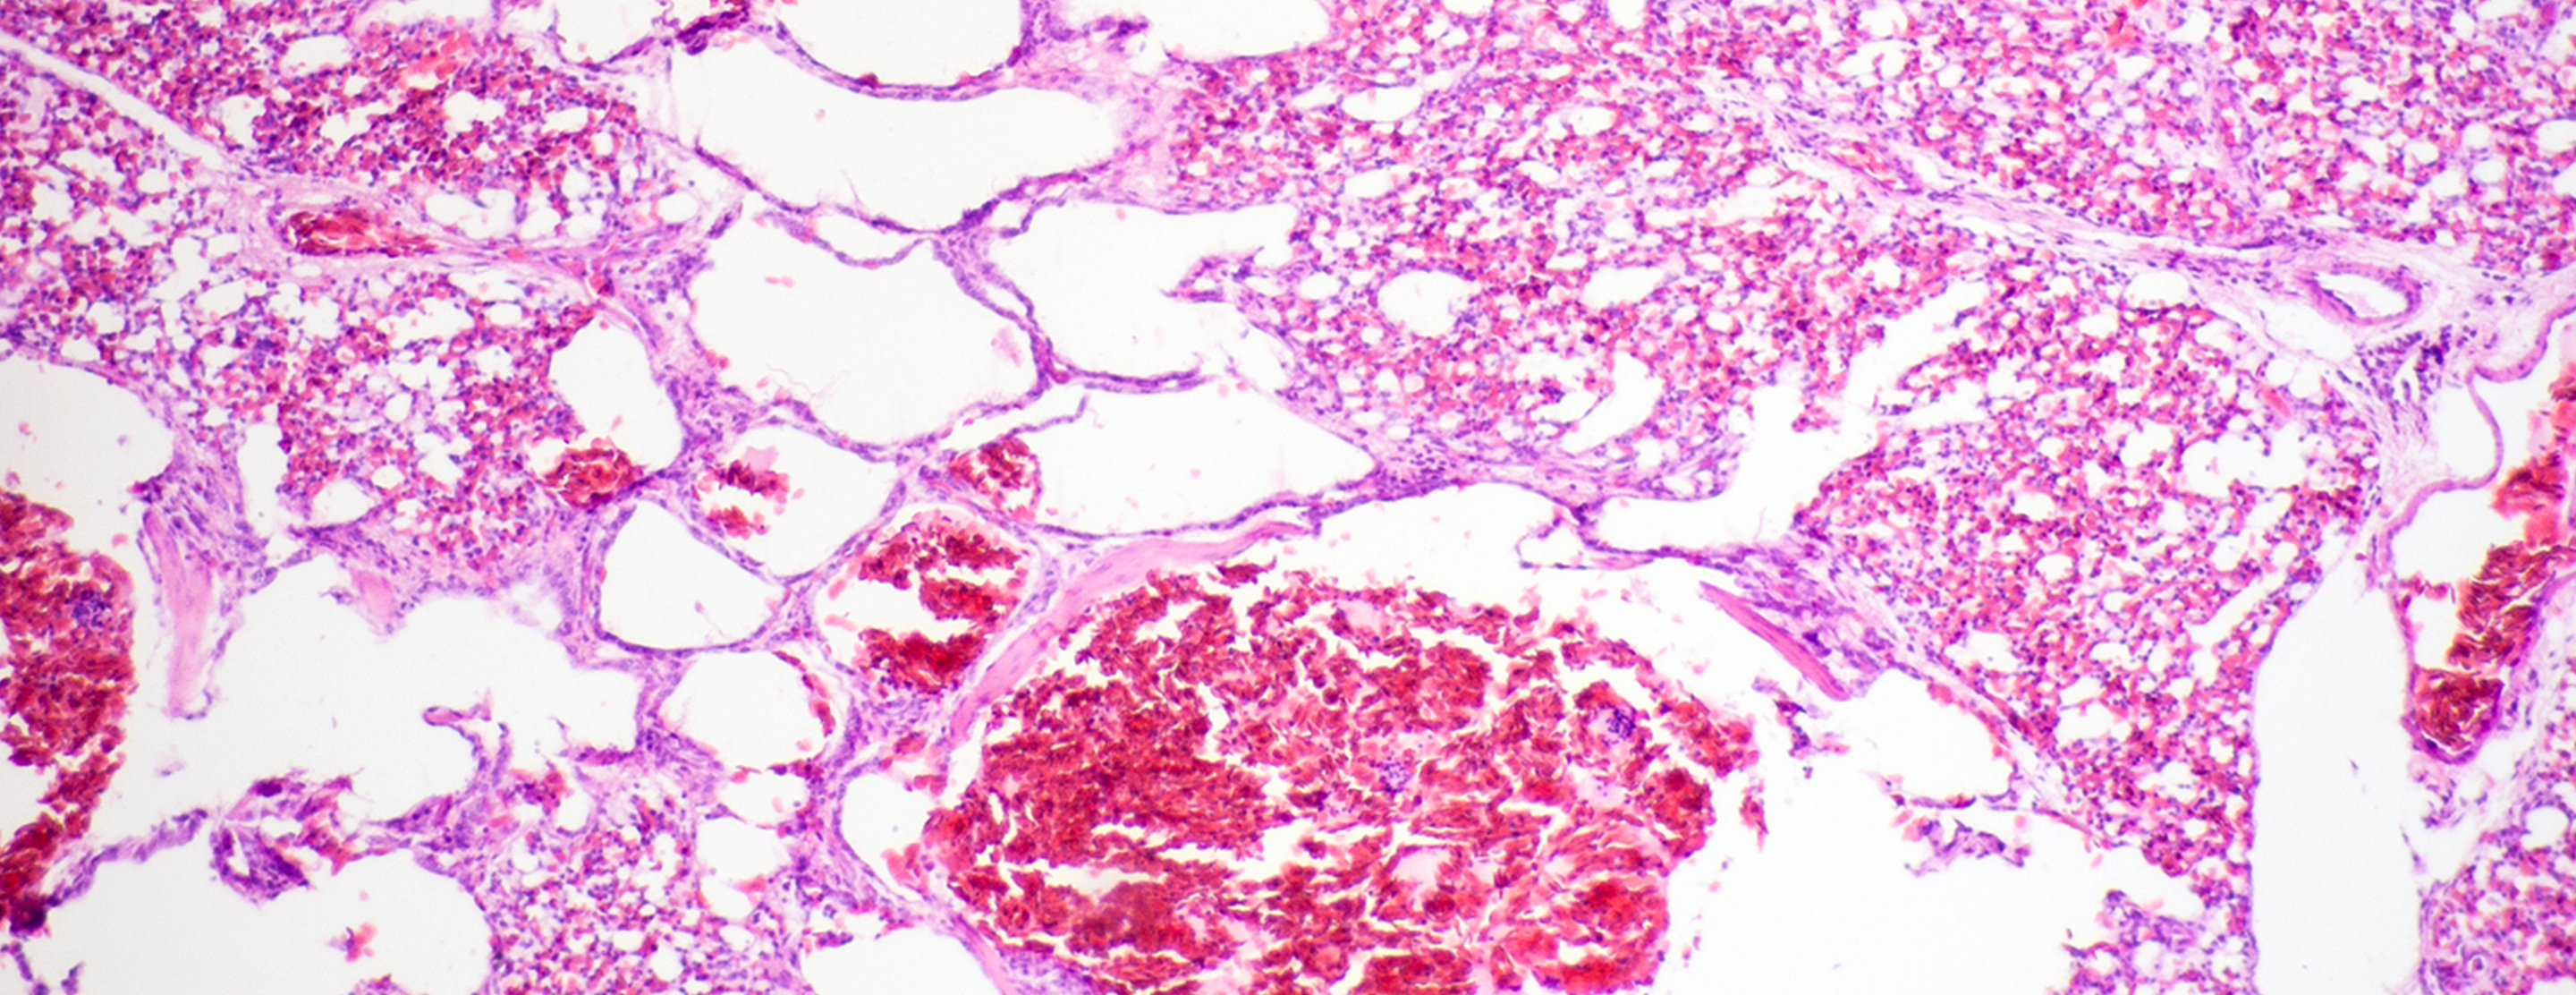

Open lung biopsy

An open lung biopsy is surgery to remove a small piece of tissue from the lung. The sample is then examined for

The open lung biopsy is done to evaluate lung problems seen on

The lungs and lung tissue will be normal.

Abnormal results may be due to:

Benign (not cancerous) tumors- Cancer

- Certain infections (bacterial, viral, fungal, or parasitic)

- Lung diseases (fibrosis)